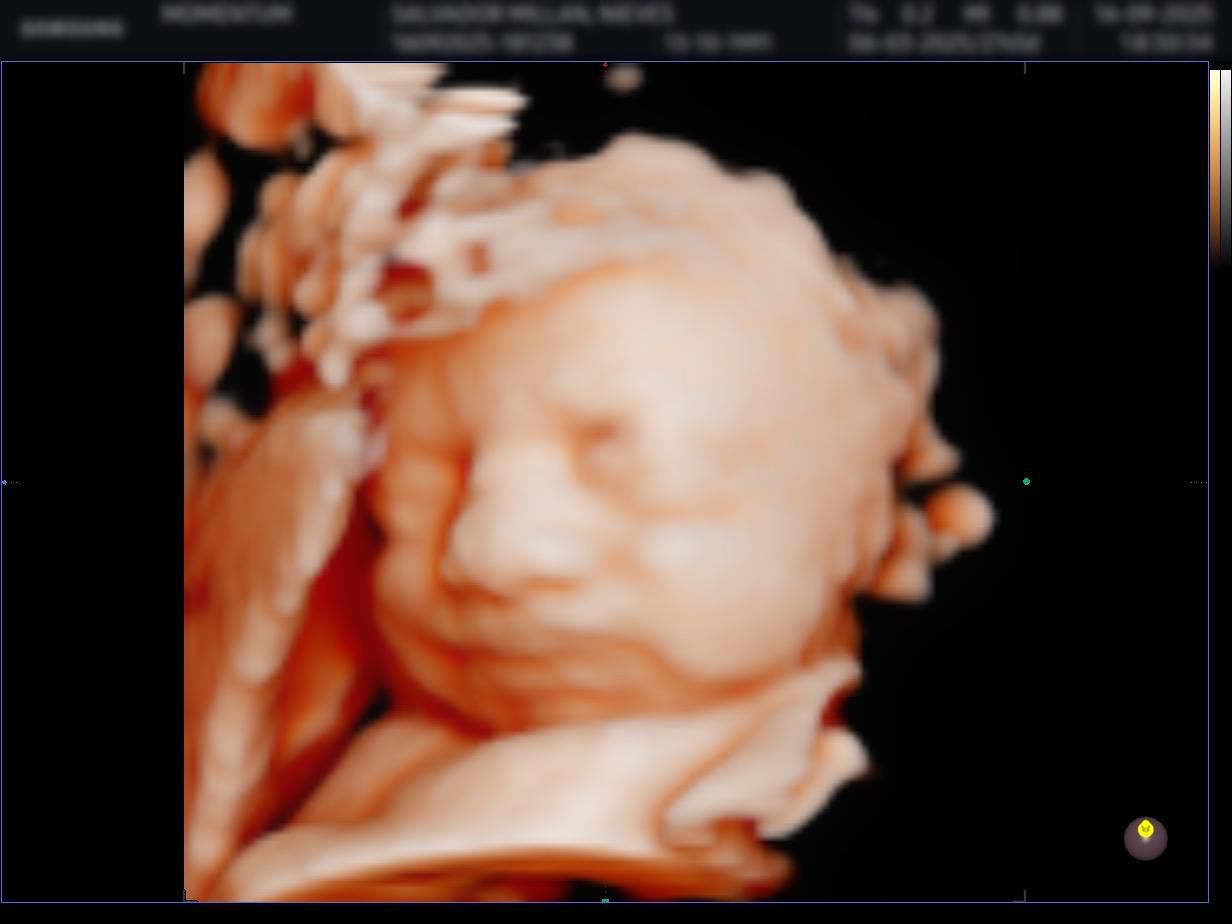

Transformamos tu ecografía en un retrato 3D interactivo con iluminación dinámica que puedes explorar moviendo tu teléfono. Descubre la nariz, las mejillas y cada detalle de tu bebé antes de nacer.

Cada imagen que ves aquí ha sido procesada por BabyFaceReveal. Arrastra el deslizador para comparar la ecografía original con el resultado 3D.

Nuestro motor analiza las texturas y estructuras visibles en la ecografía y construye un modelo 3D con profundidad, normales y desplazamiento reales.

Mueve tu teléfono o ratón para cambiar la dirección de la luz y descubre cada ángulo de la cara de tu bebé. Una experiencia única e irrepetible.

Trabaja exclusivamente con lo que ya existe en tu ecografía. Nuestro motor analiza las texturas, contornos y estructuras visibles y las reconstruye en un modelo 3D con la máxima definición. No se añaden ni inventan facciones.